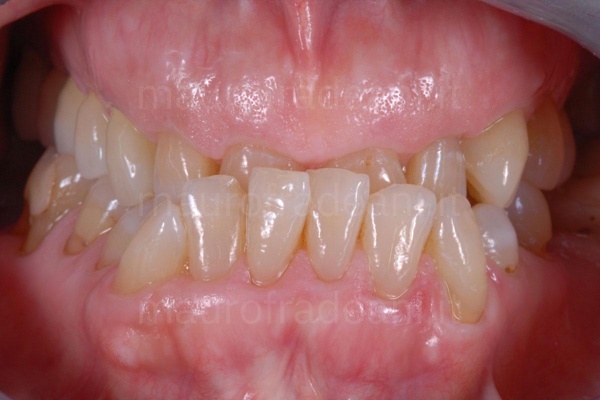

1/4: The patient presents a particularly compromised situation: considerable dental wear, multiple tooth decay and lack of teeth.

2/4: Intraoral view: the patient needs a complete rehabilitation of both arches.

3/4: Intraoral view of the cemented restorations: the esthetic-functional rehabilitation is perfectly integrated in the mouth.

4/4: The picture at the end of the treatment shows a striking change, which gives the patient the confidence of an ideal smile.